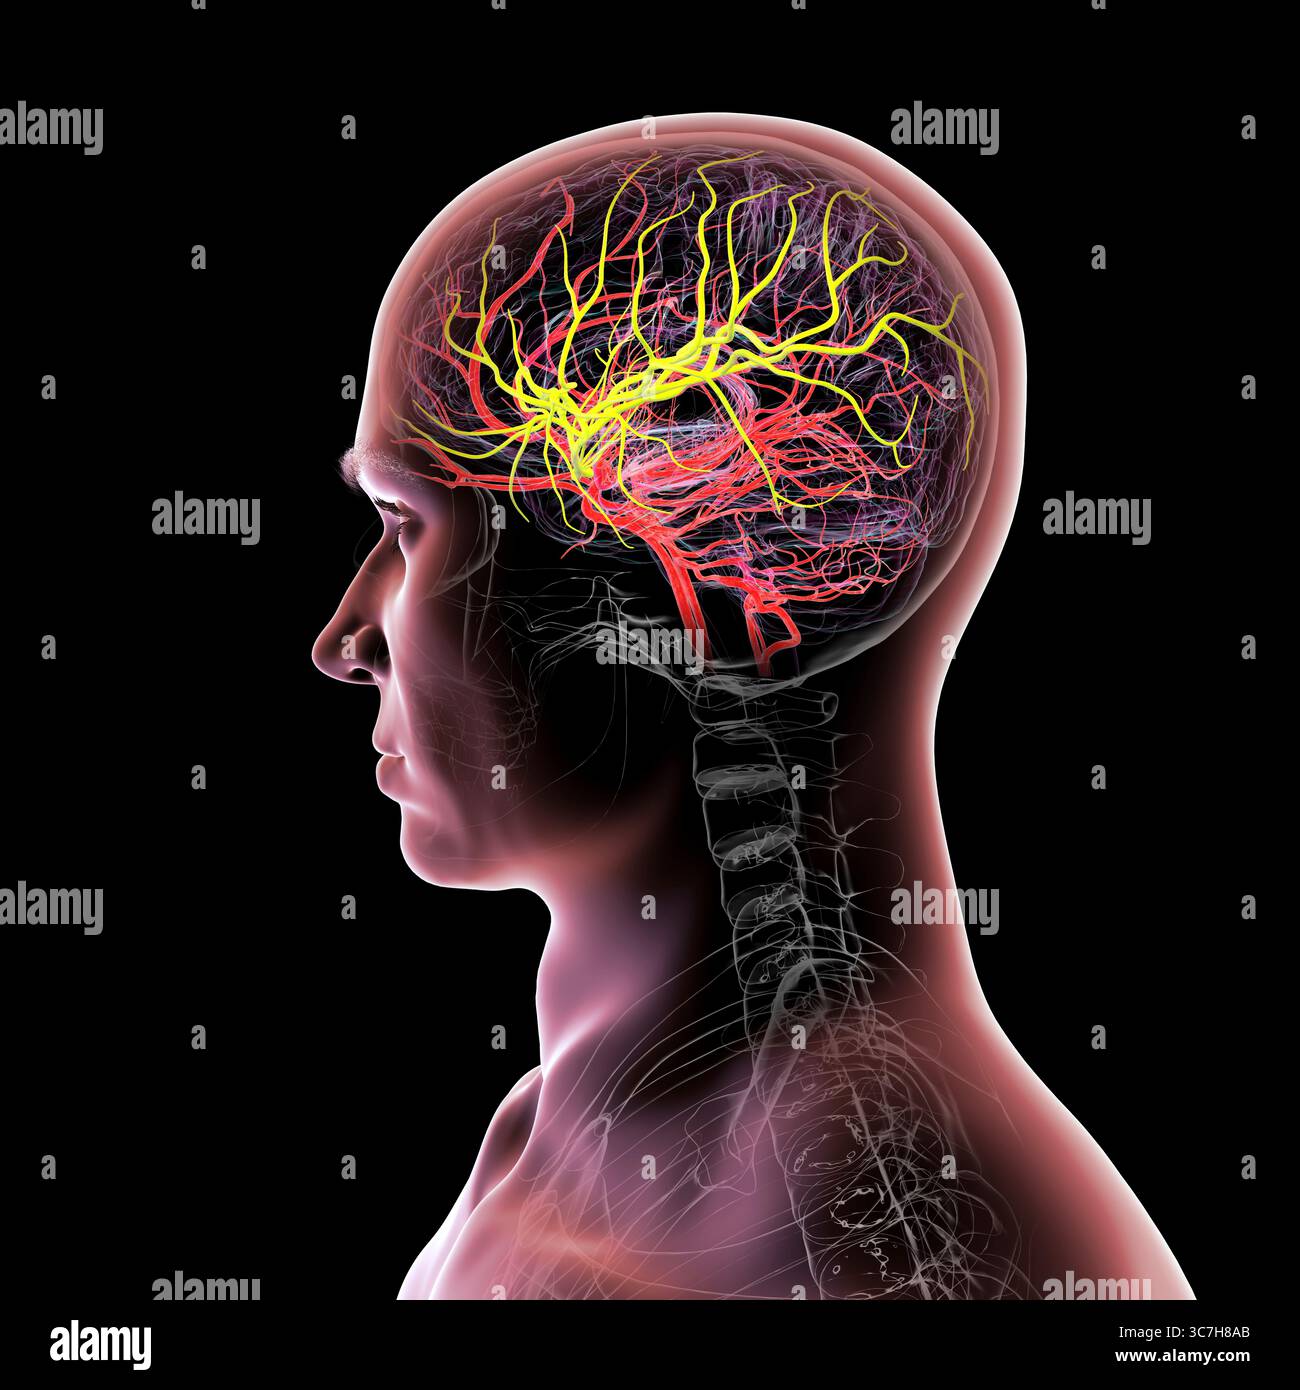

RF3C7H8AB–Darstellung der arteriellen Blutversorgung des Gehirns mit hervorgehobener Arteria cerebri Media (gelb), die Blut zu den frontalen, temporalen und parietalen Lappen liefert, entscheidend für die Gehirnfunktion.

RF3C7H897–Darstellung der arteriellen Blutversorgung des Gehirns mit hervorgehobener Arteria cerebri Media (gelb), die Blut zu den frontalen, temporalen und parietalen Lappen liefert, entscheidend für die Gehirnfunktion.

RF3C7H892–Darstellung der arteriellen Blutversorgung des Gehirns mit hervorgehobener Arteria cerebri Media (gelb), die Blut zu den frontalen, temporalen und parietalen Lappen liefert, entscheidend für die Gehirnfunktion.

RF3C7H890–Darstellung der arteriellen Blutversorgung des Gehirns mit hervorgehobener Arteria cerebri Media (gelb), die Blut zu den frontalen, temporalen und parietalen Lappen liefert, entscheidend für die Gehirnfunktion.